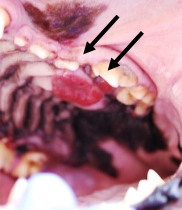

What clinical signs are seen with OMM?

visible mass (pigmented or not ~30%)

bleeding

halitosis

ptyalism

gross appearance = pigmented (67%), amelanotic (33%), ulcerated

gross appearance = red, cauliflower, ulcerated